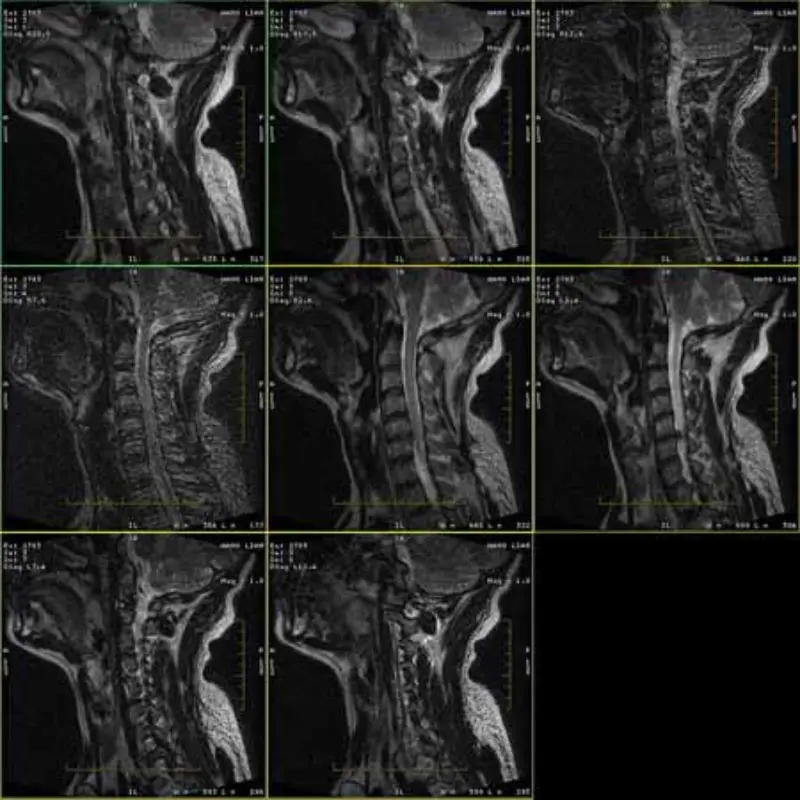

De afbeeldingen van FRFSE- en GRE-protocollen bevatten spookbeelden en soms verschijnen afbeeldingen met een lage SNR in één serie. Maar SE-protocolafbeeldingen zijn normaal.

Kijk alstublieft naar afbeeldingen bijvoegen.